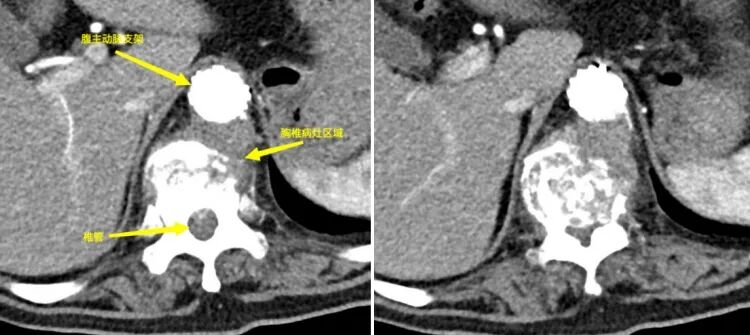

圖1.圖2:術(shù)前見腹主動(dòng)脈瘤與胸9-11椎體病灶緊密相連 圖3.圖4:動(dòng)脈瘤術(shù)前三維影像 面對(duì)這一復(fù)雜病情,貴陽市公共衛(wèi)生救治中心骨外科迅速與貴州醫(yī)科大學(xué)附屬醫(yī)院血管外科進(jìn)行溝通,共同決定采取聯(lián)合手術(shù)治療方案。在兩家單位共同努力下,患者成功進(jìn)行了降主動(dòng)脈-腹主動(dòng)脈覆膜支架腔內(nèi)隔絕術(shù)。手術(shù)后,患者的腹主動(dòng)脈瘤得到了有效控制,血管外科團(tuán)隊(duì)也順利完成了血管修復(fù)工作(圖5-6)。 圖5.圖6:降主動(dòng)脈-腹主動(dòng)脈覆膜支架腔內(nèi)隔絕術(shù)術(shù)后 隨后,貴陽市公共衛(wèi)生救治中心骨外科對(duì)患者實(shí)施了“胸椎結(jié)核病灶清除+椎體次全切除+鈦籠植骨融合+椎弓根螺釘內(nèi)固定術(shù)”(圖7-11)。手術(shù)成功地完成了胸椎結(jié)核病灶的清除,并進(jìn)行了脊柱的重建。目前,患者已經(jīng)能夠下地行走,下肢的感覺也得到了恢復(fù)。 圖7.圖8.圖9:胸椎結(jié)核術(shù)后影像 圖10.圖11:術(shù)后三維影像 “患有腹主動(dòng)脈瘤和胸椎結(jié)核的病人相對(duì)罕見,治療過程復(fù)雜且手術(shù)風(fēng)險(xiǎn)高,需要多學(xué)科的緊密合作。這次病例的成功治療,充分體現(xiàn)了貴陽市公共衛(wèi)生救治中心骨外科與貴州醫(yī)科大學(xué)附屬醫(yī)院血管外科之間的高效醫(yī)療協(xié)作和專業(yè)實(shí)力,同時(shí)也為處理類似復(fù)雜疾病提供了珍貴的臨床經(jīng)驗(yàn)?!辟F陽市公共衛(wèi)生救治中心骨外科脊柱組組長(zhǎng)任鵬醫(yī)師表示,“跨學(xué)科的聯(lián)合治療,能夠很好地應(yīng)對(duì)復(fù)雜病情,提高治療的成功率,切實(shí)為人民群眾提供安全優(yōu)質(zhì)的服務(wù)?!?/p> 貴陽市公共衛(wèi)生救治中心骨外科簡(jiǎn)介 貴陽市公共衛(wèi)生救治中心外一科(骨外科)成立于2009年11月,是省內(nèi)唯一的骨與關(guān)節(jié)結(jié)核??萍案腥竟强?。在過去的十年中,成功治療了約4500例骨結(jié)核患者,診療效果和服務(wù)享有較好口碑。目前,科室已擴(kuò)展為三個(gè)亞??平M:脊柱組、關(guān)節(jié)創(chuàng)傷組和頭頸外科組。開展脊柱、關(guān)節(jié)等骨感染疾病、頸部疾病以及骨折、脊柱關(guān)節(jié)退行性疾病、骨腫瘤手術(shù)等治療。此外,科室還負(fù)責(zé)HIV相關(guān)骨科疾病的診治工作。 患者可根據(jù)個(gè)人需求選擇骨科專家門診或普通門診服務(wù),骨外科提供全天候24小時(shí)的醫(yī)療服務(wù)。目前,科室開展了一系列具有挑戰(zhàn)性的手術(shù)治療,包括復(fù)雜脊柱(頸胸腰)、關(guān)節(jié)結(jié)核手術(shù)、四肢關(guān)節(jié)創(chuàng)傷及椎體成形術(shù)、初次人工全髖關(guān)節(jié)置換術(shù)、初次復(fù)雜及人工髖關(guān)節(jié)翻修術(shù)、初次人工膝關(guān)節(jié)置換術(shù)、復(fù)雜初次及人工膝關(guān)節(jié)翻修術(shù)、嚴(yán)重粉碎性骨盆及髖臼骨折等。此外,科室還涵蓋綜合醫(yī)院骨科大部分常見、多發(fā)疾病的手術(shù)及保守治療??剖遗鋫淞酥行虲臂X光機(jī)、電動(dòng)磨鉆、骨折治療儀、中頻/低頻治療儀、下肢CPM功能鍛煉器、空氣壓力波等多種先進(jìn)設(shè)備。針對(duì)脊柱、關(guān)節(jié)疾病患者的主要臨床癥狀,如頸肩疼痛、腰腿疼痛、四肢關(guān)節(jié)疼痛、下肢活動(dòng)障礙等,科室還開展了中藥穴位貼敷、藥棒穴位按摩、艾灸等特色中醫(yī)治療,以滿足臨床需求,為患者提供高質(zhì)量的服務(wù)。 咨詢電話:0851-85959033